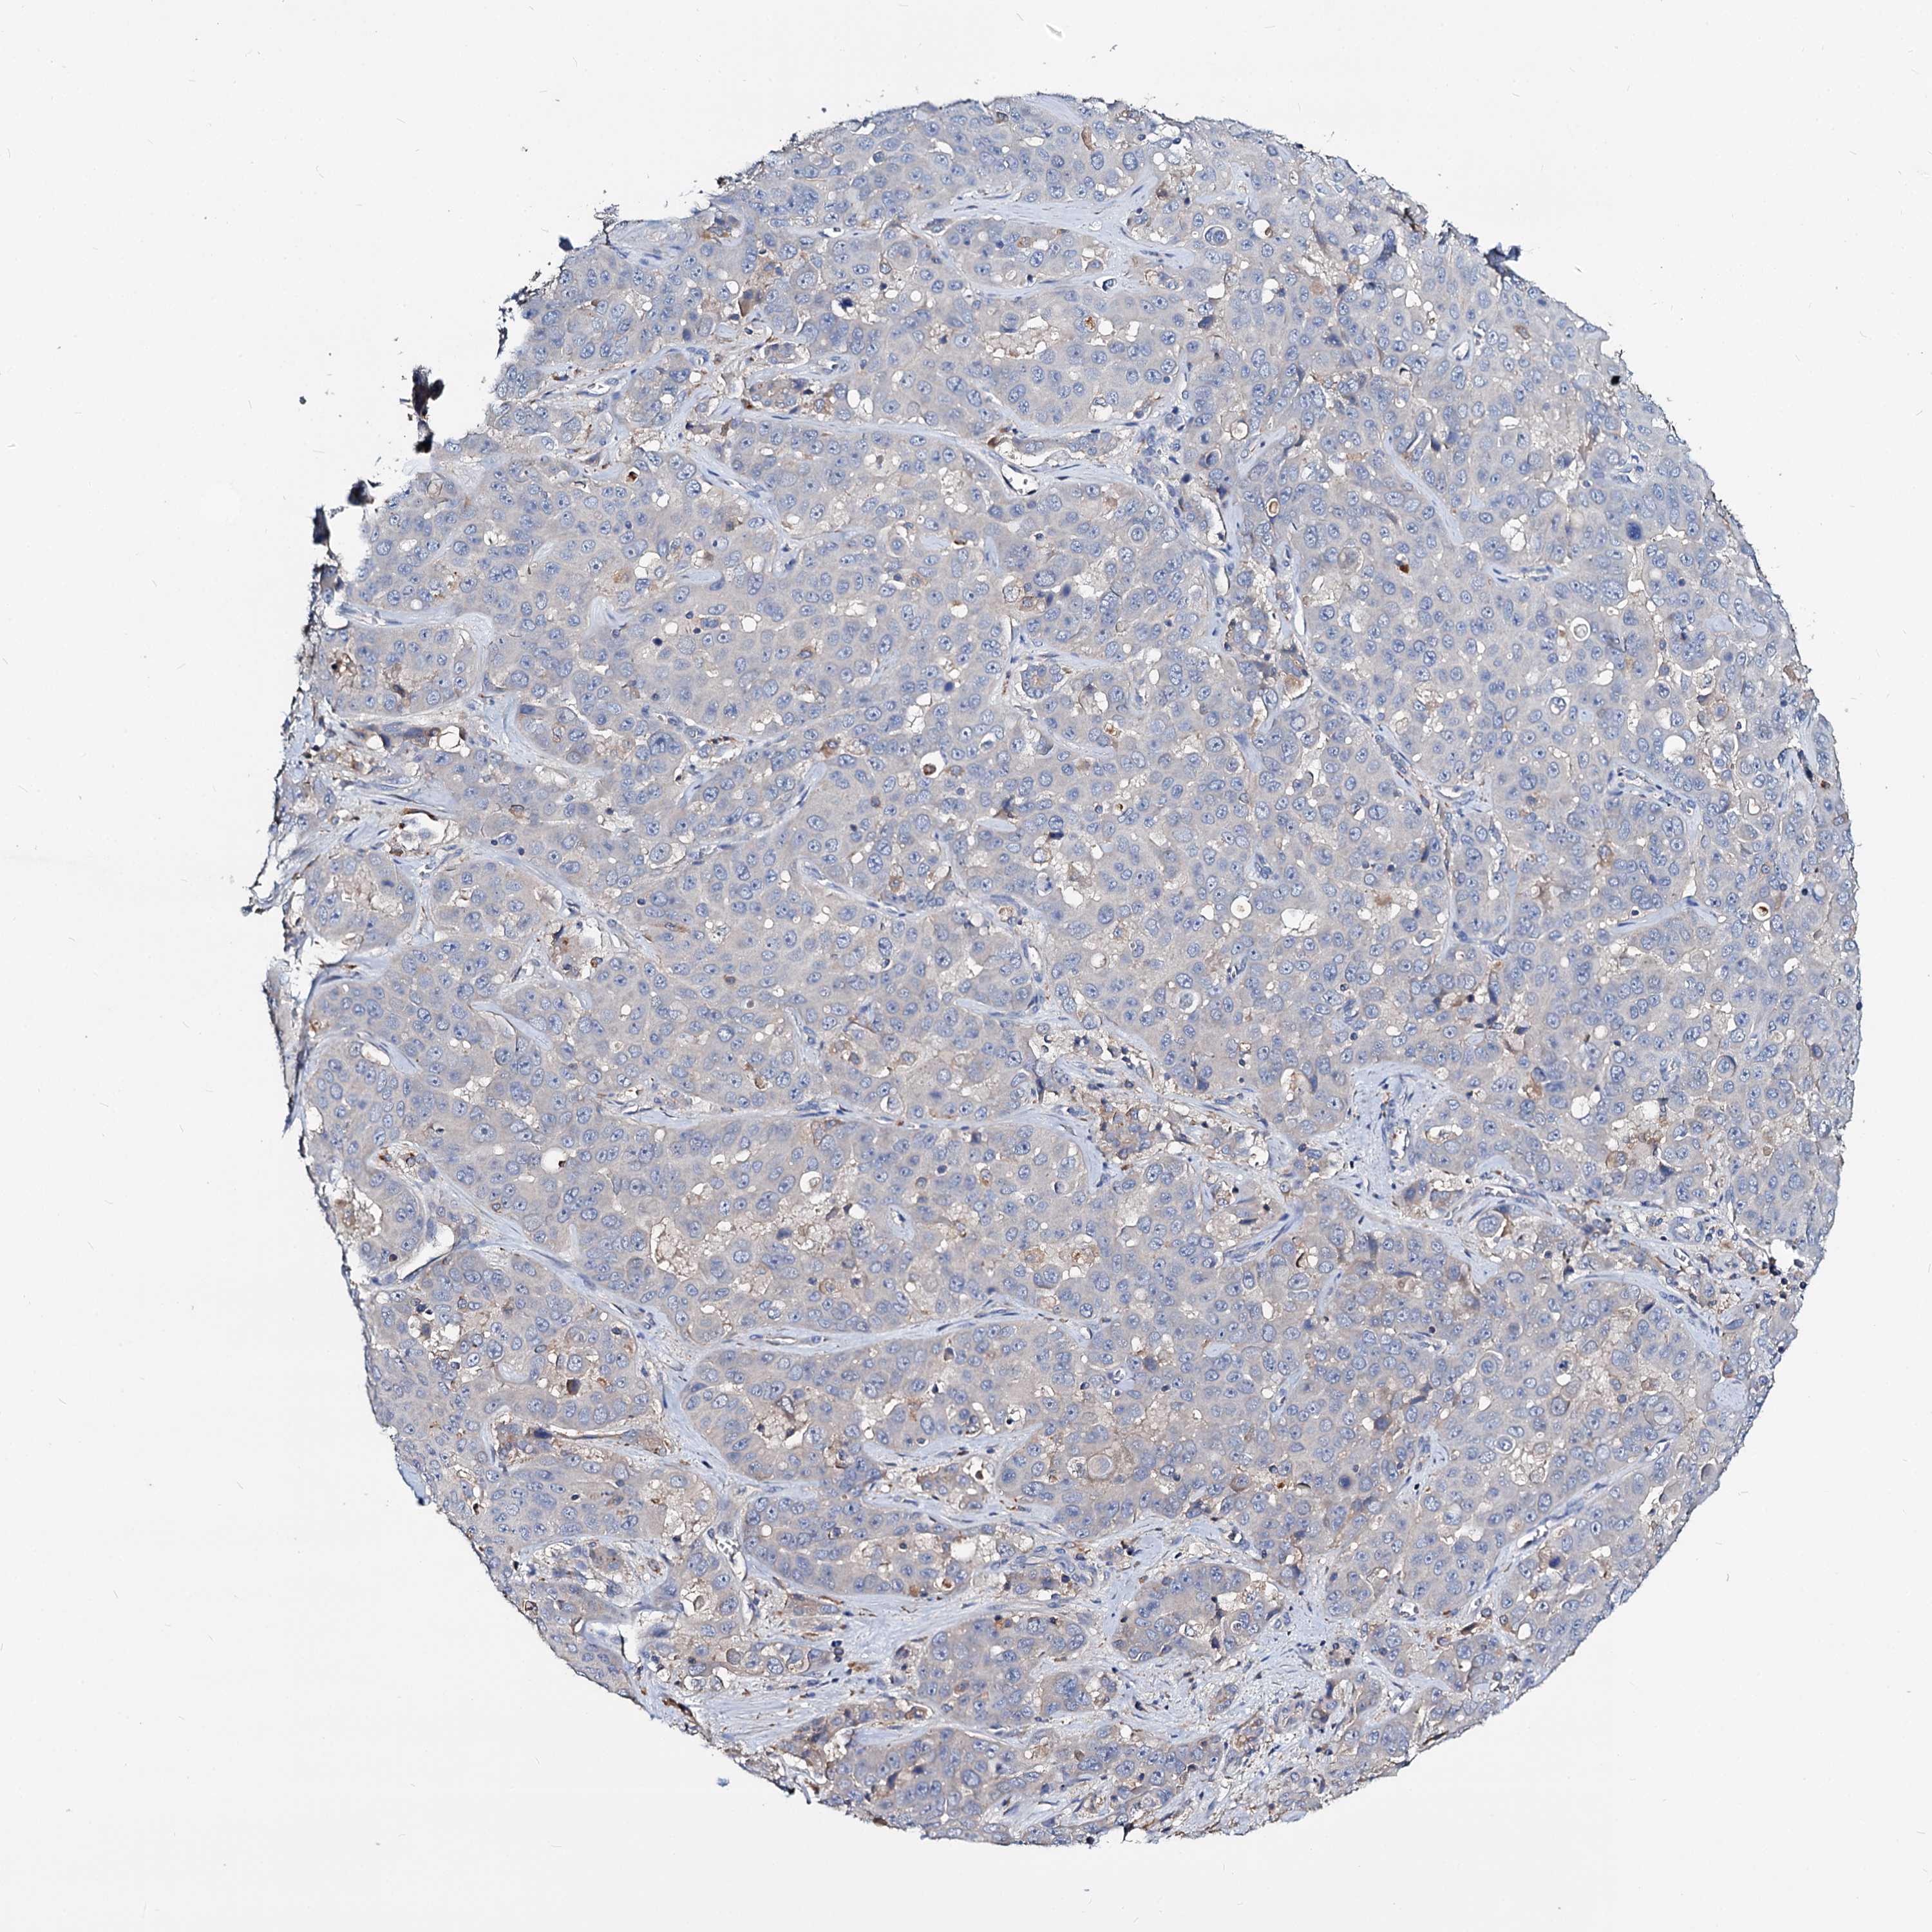

LIVER CANCER - Protein expressioni

A mouse-over function shows sample information and annotation data. Click on an image to view it in a full screen mode. Samples can be filtered based on level of antibody staining by selecting one or several of the following categories: high, medium, low and not detected. The assay and annotation is described here.

Note that samples used for immunohistochemistry by the Human Protein Atlas do not correspond to samples in the TCGA dataset.

Antibody stainingi

Antibody staining in the annotated cell types in the current human tissue is reported as not detected, low, medium, or high, based on conventional immunohistochemistry profiling in selected tissues. This score is based on the combination of the staining intensity and fraction of stained cells.

Each image is clickable and will lead to virtual microscopy that enables deeper exploration of all samples and also displays staining intensity scores, fraction scores and subcellular localization as well as patient and tissue information for each sample.

Antibody HPA039219

Antibody HPA048187

Staining

High

Medium

Low

Not detected

Intensity

Strong

Moderate

Weak

Negative

Quantity

>75%

75%-25%

<25%

None

Location

Nuclear

Cytoplasmic/membranous

Cytoplasmic/membranous,nuclear

Cholangiocarcinoma

Carcinoma, Hepatocellular, NOS